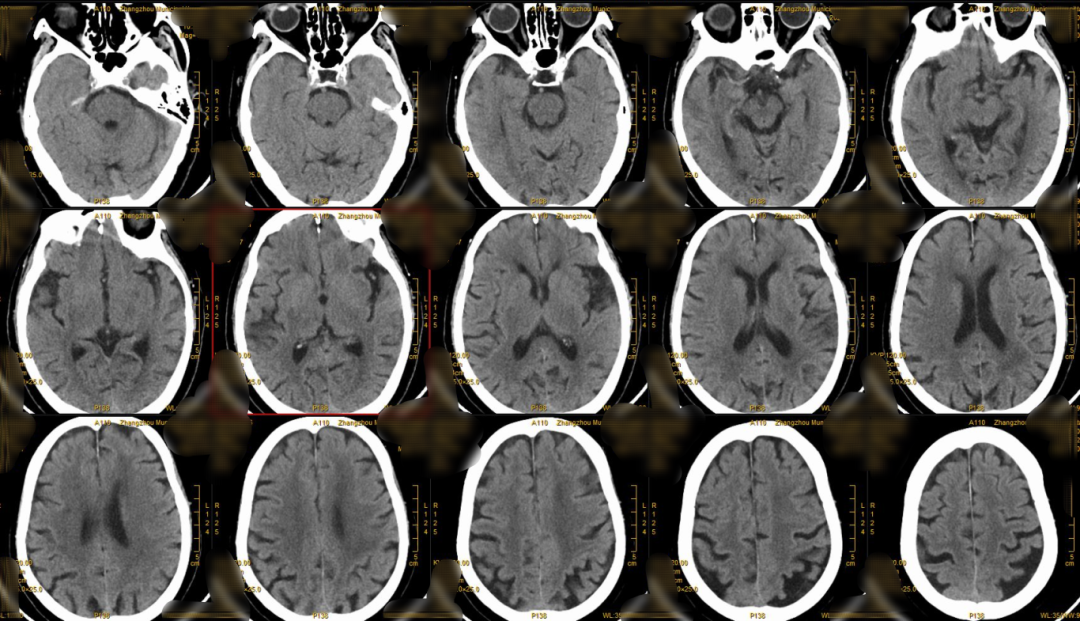

颅脑CT:ASPECT 10分。

术后CT:基底节区稍高密度影,考虑血脑屏障破坏,未见明显出血。

什么叫桡鞘【例久弥新】寻道于桡——瑞康通5.5F IntroSky X导管鞘经桡动脉行右侧大脑中动脉取栓一例_https://www.jmylbn.com_新闻资讯_第26张

术后CTA:CTA提示血管再通良好,予桥接双联抗血小板聚集治疗。